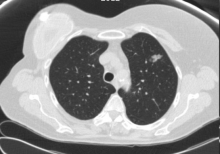

A 70-year-old woman with a past history of breast cancer in 2004 also had a nonperipheral pseudonodular ground glass appearance lesion in the left upper lobe since 2010, a core-needle biopsy in 2012 and 2015, and a diagnosis of benign pneumocytoma (Figure 1). Since 2018, the lesion had a growth of the solid component in chest computed tomography scan, so a positron emission tomography scan was performed, which showed an increased metabolic uptake in the lesion (SUV max 2.77) (Figure 2).

Figure 1